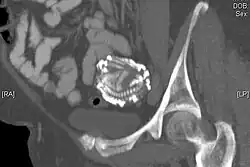

A CT scan showing an extra-uterine calcified foetal skeleton, a lithopedion